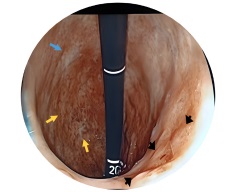

En el control endoscópico de junio del año 2023, se objetivó a nivel del tercio distal del cuerpo gástrico, en la cara posterior, una lesión de 30 mm, de bordes elevados, congestivos, con un área de depresión central (Figura 1). Se le practicó una biopsia, con resultado de presencia de metaplasia intestinal incompleta (en el 20 %) y atrofia. Ante los hallazgos, se decidió realizar una nueva endoscopía con cromoendoscopía en octubre del 2023, y se evidenció la lesión descrita previamente, que a la instilación con ácido acético mostró una reacción positiva a nivel de depresión. Se tomó otra biopsia, con resultado de adenocarcinoma tubular infiltrante moderadamente diferenciado (Figura 2).

Figura 1 Gastroscopia en maniobra de retroversión (u-turn). Lesión de 30 mm, de bordes elevados, congestivos, con área de depresión central en el cuerpo gástrico (flechas negras). Se aprecia, además, gastritis actínica (flechas amarillas) y lesiones cicatrizadas antiguas (flecha azul) con relación al tratamiento descrito en el antecedente (terapia concurrente de radioterapia y quimioterapia).